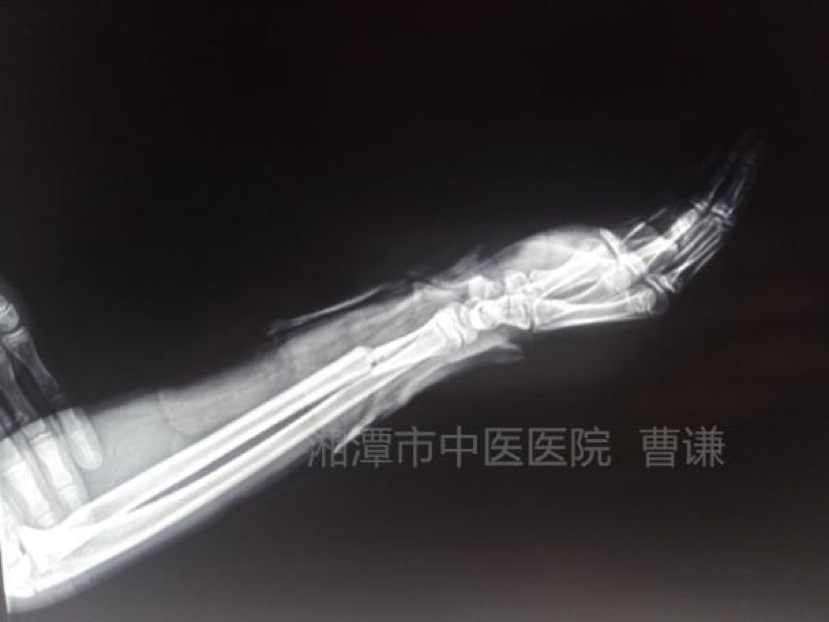

我们来看看下面这例 66 岁的女性患者。外伤后拍片示:桡骨中下段骨折、断端错位明显,下尺桡关节分离。

患者外伤后拍片示:右桡骨中下段骨折,下尺桡关节分离。